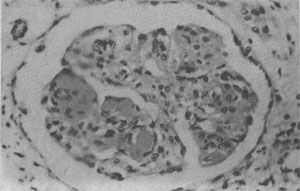

图4-10 狼疮性肾小球肾炎

肾小球毛细血管丛节段性纤维素样坏死,伴系膜细胞增生;间质炎细胞浸润